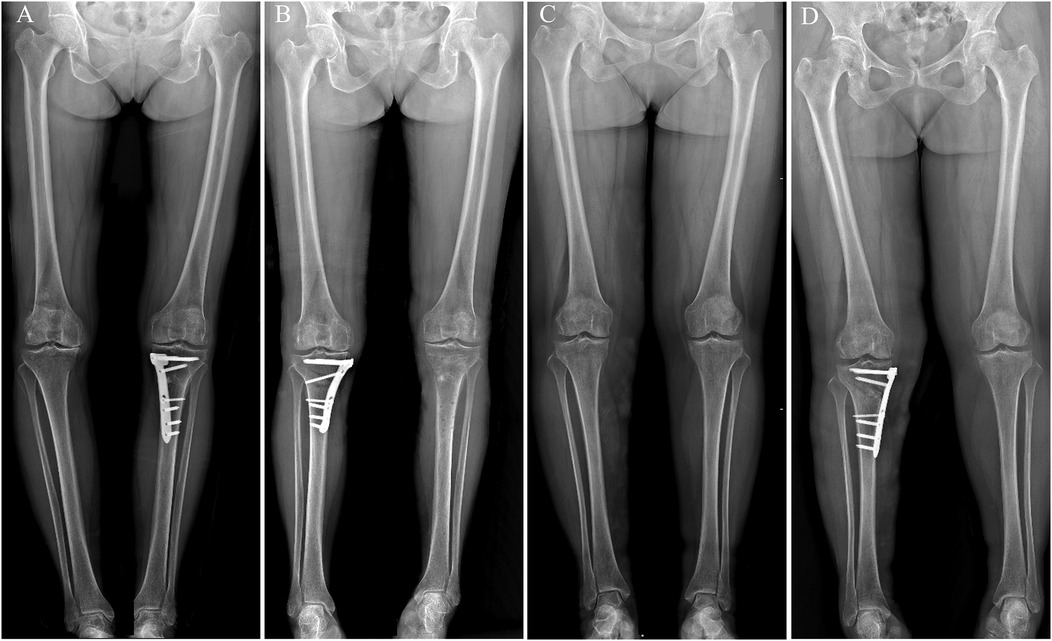

Background: High tibial osteotomy (HTO) corrects varus malalignment and unloads the medial knee compartment, yet the conventional T-shaped locking plate may cause discomfort due to suboptimal anatomic conformity. We developed a novel locking plate to improve anatomic fit and fixation stability and compared it with the T-shaped plate in Anterior Popliteus Transtibial-tuberosity high tibial osteotomy (APTT-HTO). Methods: This single-center retrospective observational comparative study included 14 consecutive patients who underwent APTT-HTO between August 2024 and June 2025. Patients were grouped by implant type (novel plate: n = 7; T-shaped plate: n = 7). Postoperative CT quantified plate orientation/position, plate–bone conformity (gap and position mismatch), screw alignment, and standard alignment parameters (hip–knee– ankle angle [HKA], posterior tibial slope [PTS]). Results: The novel plate showed more posteromedial placement and superior anatomic conformity. The plate angle relative to the posterior tibial condylar reference line was larger with the novel plate (74.49° ± 8.76°) than with the T-shaped plate (62.62° ± 7.05°, P<0.05). The proximal central screw–plate angle was smaller (5.70° ± 4.80° vs 27.48° ± 6.05°, P<0.05), the plate–bone gap was reduced (1.84 ± 0.68 mm vs 2.98 ± 0.38 mm, P<0.05), and plate position mismatch was lower (20.20% ± 7.70% vs 37.70% ± 10.00%, P<0.05). Proximal and distal offsets considered separately were not significantly different (P>0.05). Both groups achieved the planned coronal correction, and sagittal PTS remained stable (P>0.05). Conclusions: In this CT-based cohort, the novel anatomically contoured locking plate achieved superior anatomic conformity in APTT-HTO—characterized by more posteromedial positioning, a more favorable screw trajectory, and improved plate–bone apposition—compared with a conventional T-shaped plate. These findings warrant confirmation in larger, prospective studies.